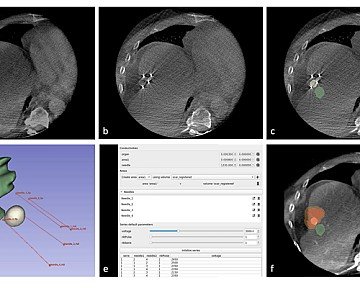

L'équipe-projet Monc du Centre Inria de l’université de Bordeaux, spécialisée en modélisation mathématique pour l’oncologie, travaille notamment sur ce type de maladie. Pour cela, les scientifiques de l’équipe analysent les lames histologiques issues de biopsies ou de pièces chirurgicales. Ces lames, teintées pour révéler les noyaux et les cellules, offrent des images d'une résolution extrêmement élevée (jusqu'à 100 000 pixels par 100 000). La taille colossale de ces images rend leur analyse intégrale difficile, mais grâce aux travaux de l’équipe-projet Monc, il est tout de même possible d’en tirer des informations essentielles

Pour traiter ces images, la méthode consiste à les diviser en tuiles, c’est-à-dire des sous-ensembles d'images plus petites, facilitant ainsi leur gestion. Chaque lame peut être découpée en environ 10 000 tuiles, permettant un travail de classification à partir d'un échantillonnage représentatif. Les scientifiques de l’équipe utilisent ensuite de l'apprentissage profond multi-instance, c’est-à-dire une technique d’intelligence artificielle où un ordinateur va apprendre à partir de nombreuses petites parties (ici les tuiles) d’une grande image (la lame), afin de comprendre et de prendre des décisions sur l’ensemble sans avoir à tout analyser d’un coup. Ce processus permet de caractériser le profil biologique des échantillons et d'anticiper la réponse au traitement ou le risque de rechute.

Pour harmoniser les données provenant de diverses sources, l'équipe-projet Monc travaille sur des algorithmes capables de normaliser les différences de coloration entre les lames. Cela permet d'appliquer des méthodes d'apprentissage multiensembles robustes malgré les variations.